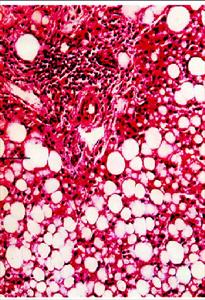

·脂肪變性

脂肪變性1、肝脂肪變性:肝細胞脂肪酸代謝過程的某個或多個環節,由於各種因素的作用而發生異常,可引發脂肪變性。

肉眼可見肝增大,邊緣鈍、色淡黃、較軟,切面油膩感。鏡下:重度脂肪變的肝細胞,其胞核被胞漿內蓄積的脂肪壓向一側,形似脂肪細胞,並可彼此融合成大小不等的脂囊。脂肪變性在肝小葉中的分布與其病因有關,例如肝淤血時小葉中央區缺氧最嚴重,所以脂肪變性首先在此處發生,長期淤血後,小葉中央區細胞大多萎縮、變性或消失,於是小葉周邊區細胞也發生缺氧而發生脂肪變性。磷中毒時,肝細胞脂肪變性主要發生在肝小葉周邊區。肝細胞脂肪變性通常不引起肝功能障礙,重度脂肪變性的肝細胞可壞死,並可繼發肝硬化。